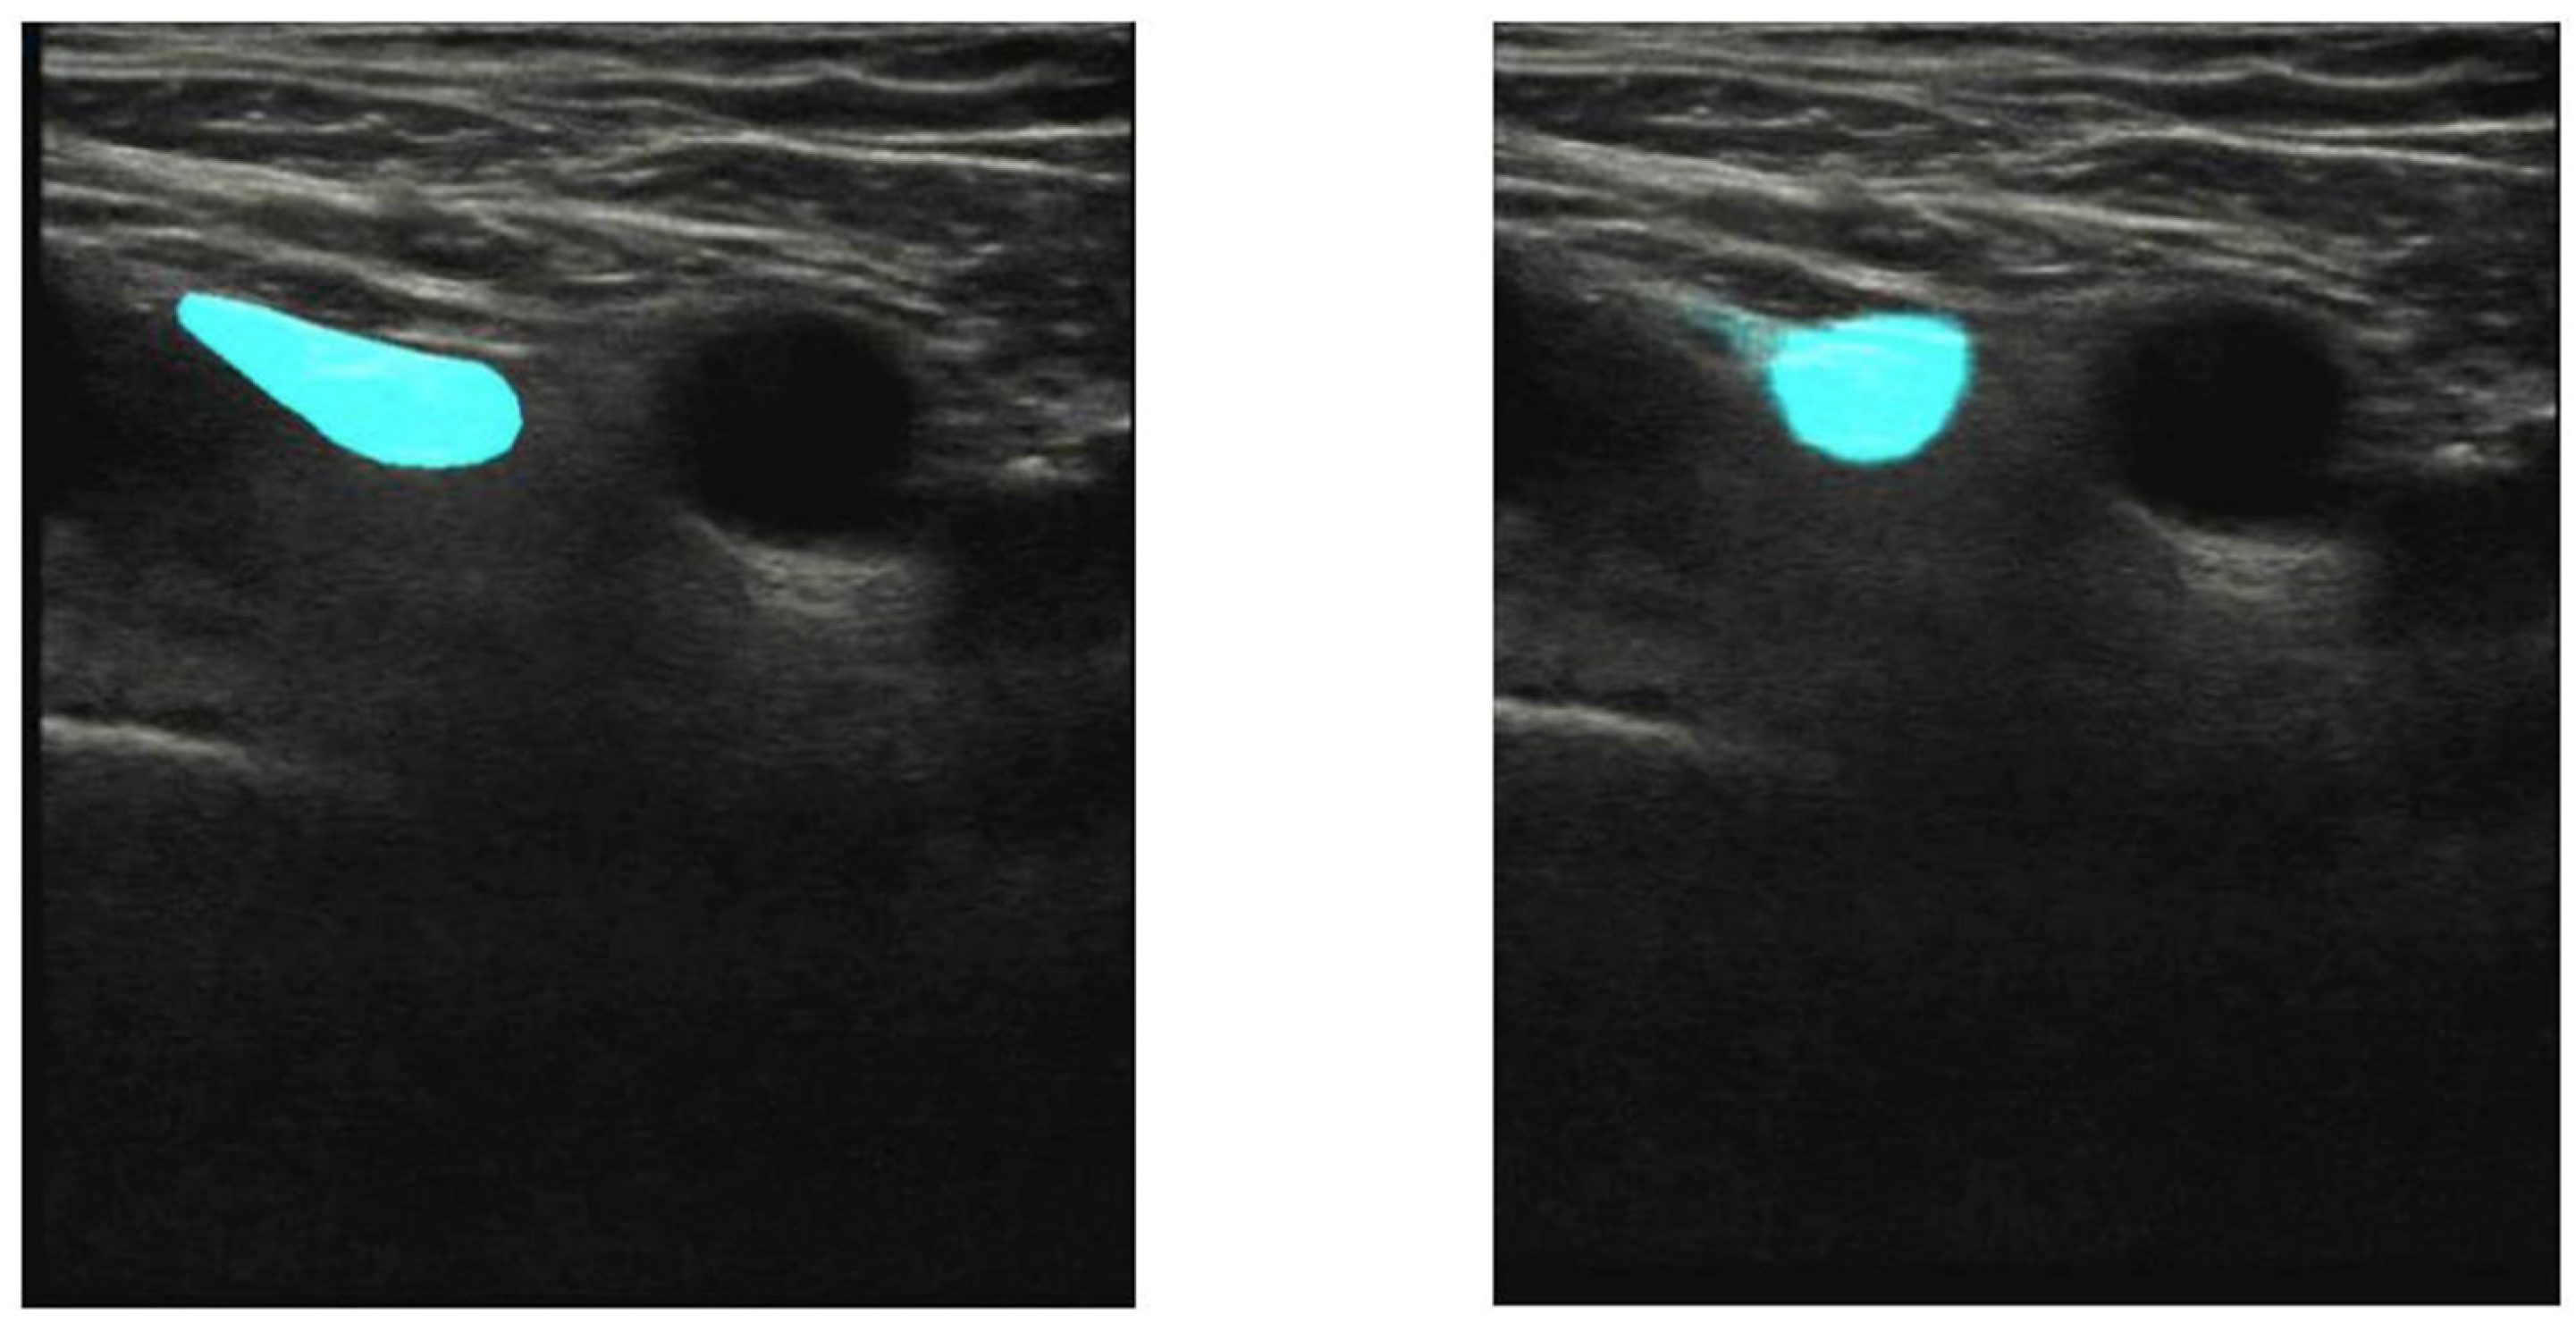

- Bowness, J.; Varsou, O.; Turbitt, L.; Burkett-St Laurent, D. Identifying anatomical structures on ultrasound: Assistive artificial intelligence in ultrasound-guided regional anesthesia. Clin. Anat. 2021, 34, 802–809. [Google Scholar] [CrossRef] [PubMed]

- Bowness, J.; Burckett-St Laurent, D.; Hernandez, N.; Keane, P.A.; Lobo, C.; Margetts, S.; Moka, E.; Pawa, A.; Rosenblatt, M.; Sleep, N.; et al. Assistive artificial intelligence for ultrasound image interpretation in regional anesthesia: An external validation study. Br. J. Anaesth. 2023, 130, 217–225. [Google Scholar] [CrossRef]